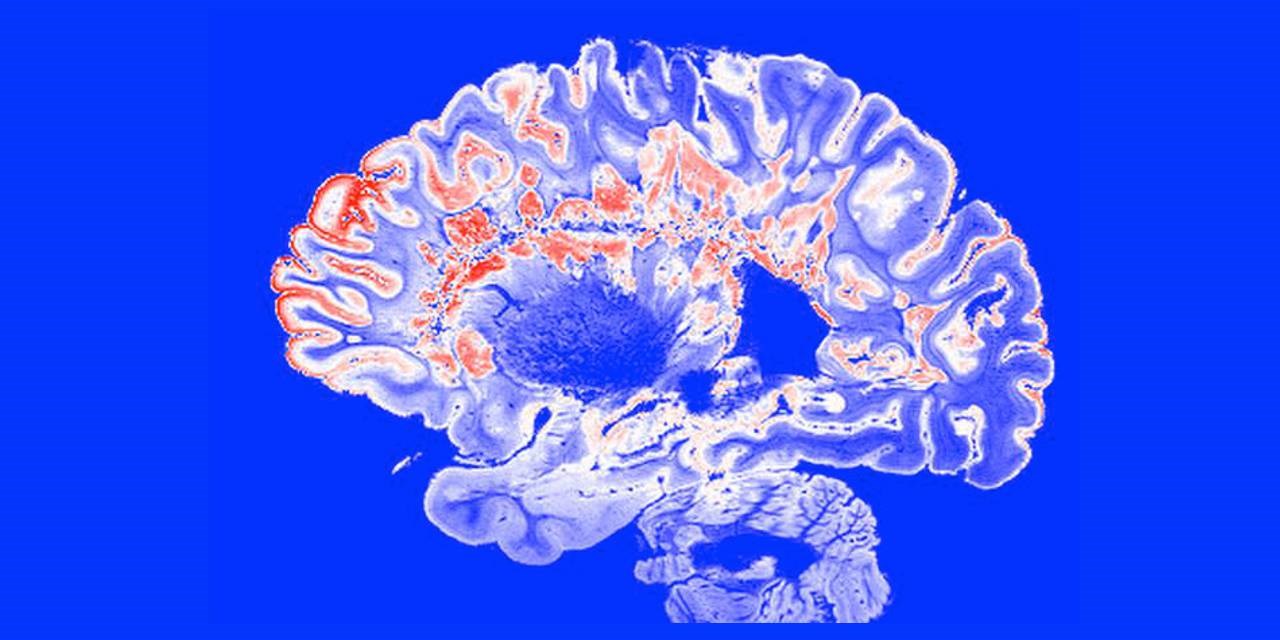

Рассеянный склероз — это опосредованное иммунитетом заболевание центральной нервной системы, при котором Т-лимфоциты атакуют миелиновые оболочки нервов. В результате нервные волокна теряют способность проводить импульс, и «потоки информации» между мозгом и периферией прерываются. В мозге также наблюдается разрушение белого вещества. На снимках МРТ повреждения (склеры) выглядят как «бляшки» или «дырки» — они являются одним из характерных признаков рассеянного склероза. Другим неотъемлемым признаком заболевания является воспаление, которое является следствием активации Т-лимфоцитов.